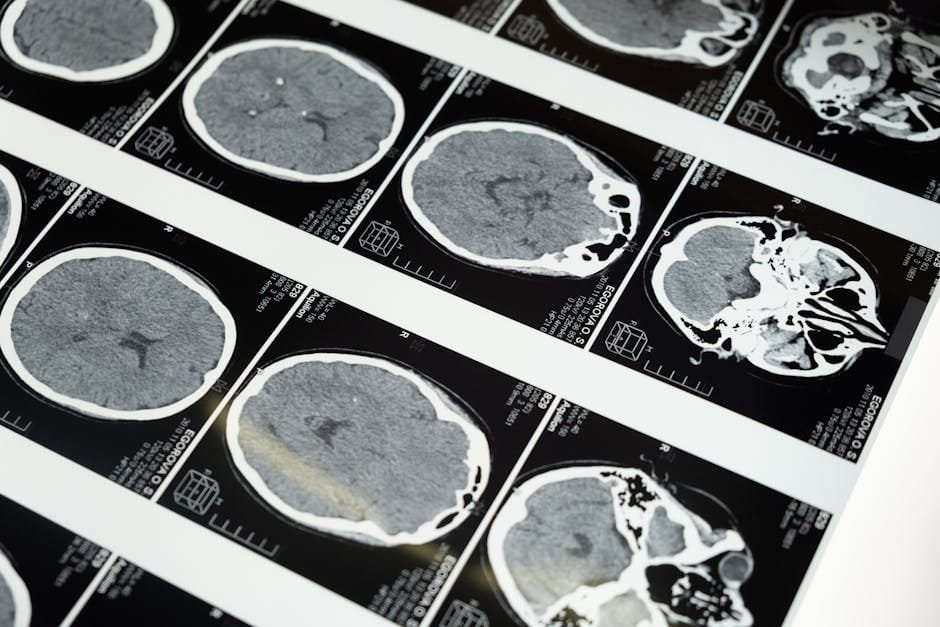

A GraidMedical egy innovatív teleradiológiai csapat, amelyet a korszerű egészségügy iránti elhivatottság vezérel.

Radiológusaink és adat-tudósaink egy közös cél érdekében dolgoznak: hogy pácienseink és partnereink számára a legmodernebb technológiát és szakértelmet nyújtsuk.

Küldetésünk, hogy a radiológia területén kiemelkedő minőséget biztosítsunk, mindezt az innováció, a pontosság és a betegek iránti elkötelezettség jegyében.

Hisszük, hogy a technológia és az orvosi szakértelem ötvözése javítja az életminőséget, és biztonságot nyújt mind a betegek, mind az egészségügyi szakemberek számára.